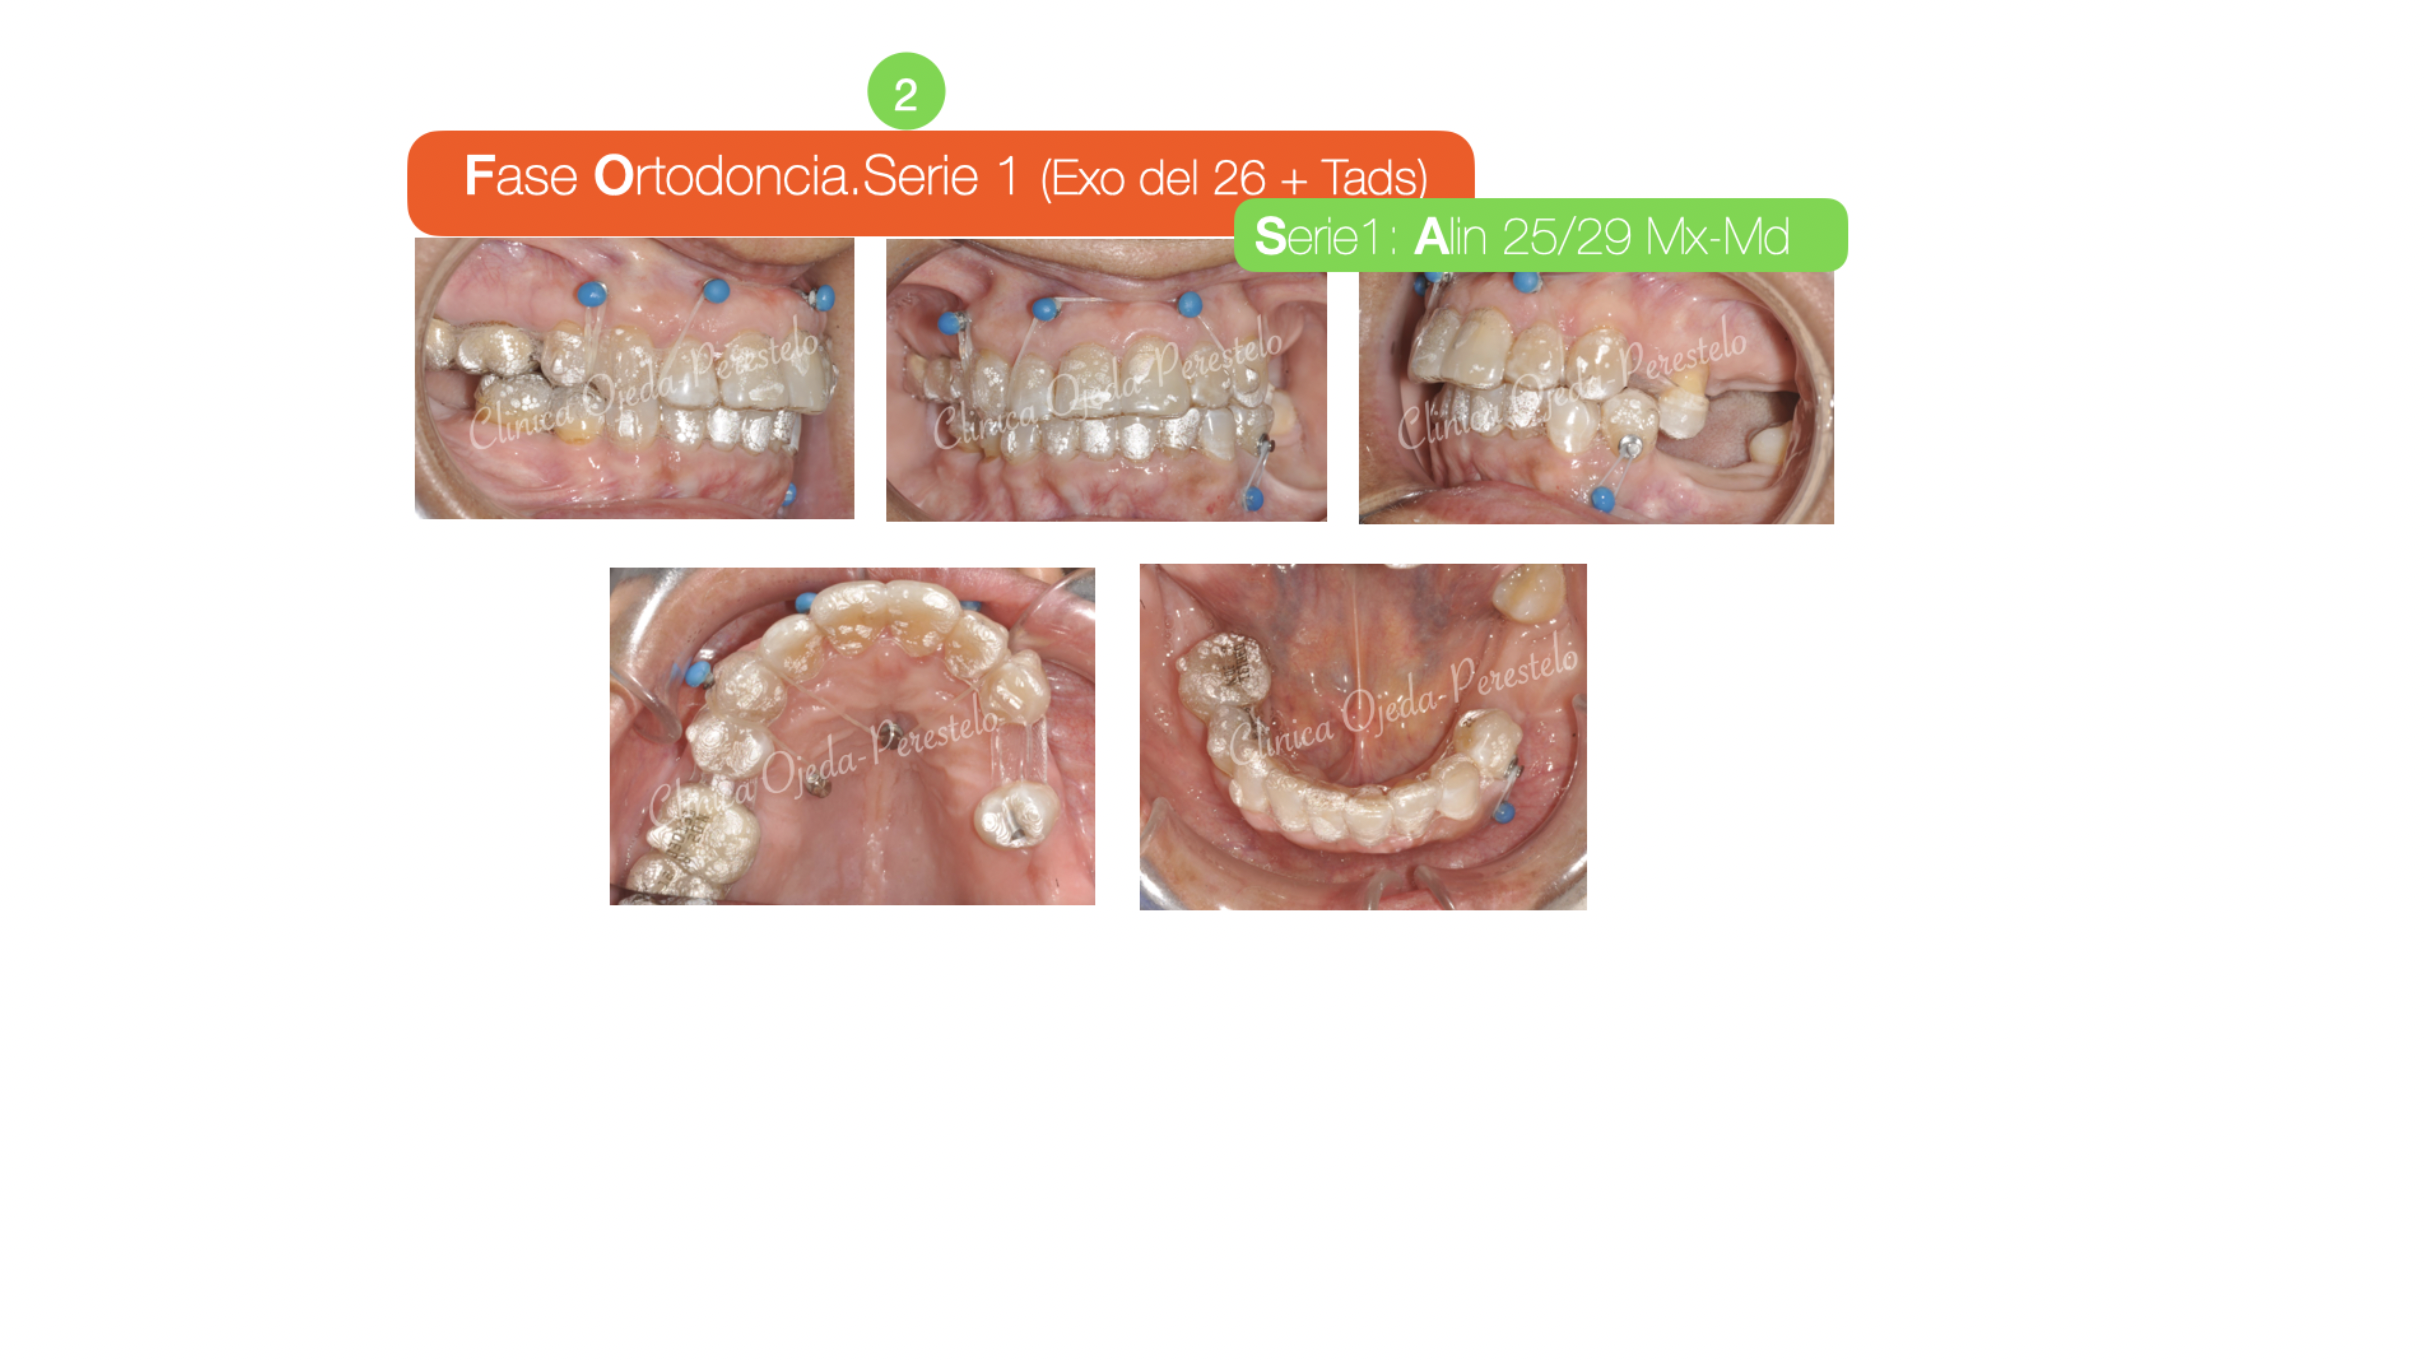

El objetivo de la etapa ortodóncica no era otro que alinear y nivelar sus arcadas dentarias y adecuar los espacios para la colocación (futura) de implantes y pónticos. Al tratarse de una paciente con limitación de apertura y el plano Maxilar inclinado y descendido en el lado derecho, se decidió combinar alineadores transparentes (Sistema Invisalign) con Microtornillos estratégicamente colocados.

Una vez finalizada la fase ortodóncica comenzamos con la colocación de sus implantes y coronas. En total sumaron 81 maxilares y 75 mandibulares que la paciente se cambiaba semanalmente. En la actualidad la paciente se encuentra una vez colocados sus implantes y coronas con una última serie de alineadores a efectos de conseguir un mejor detallado ortodóncico.